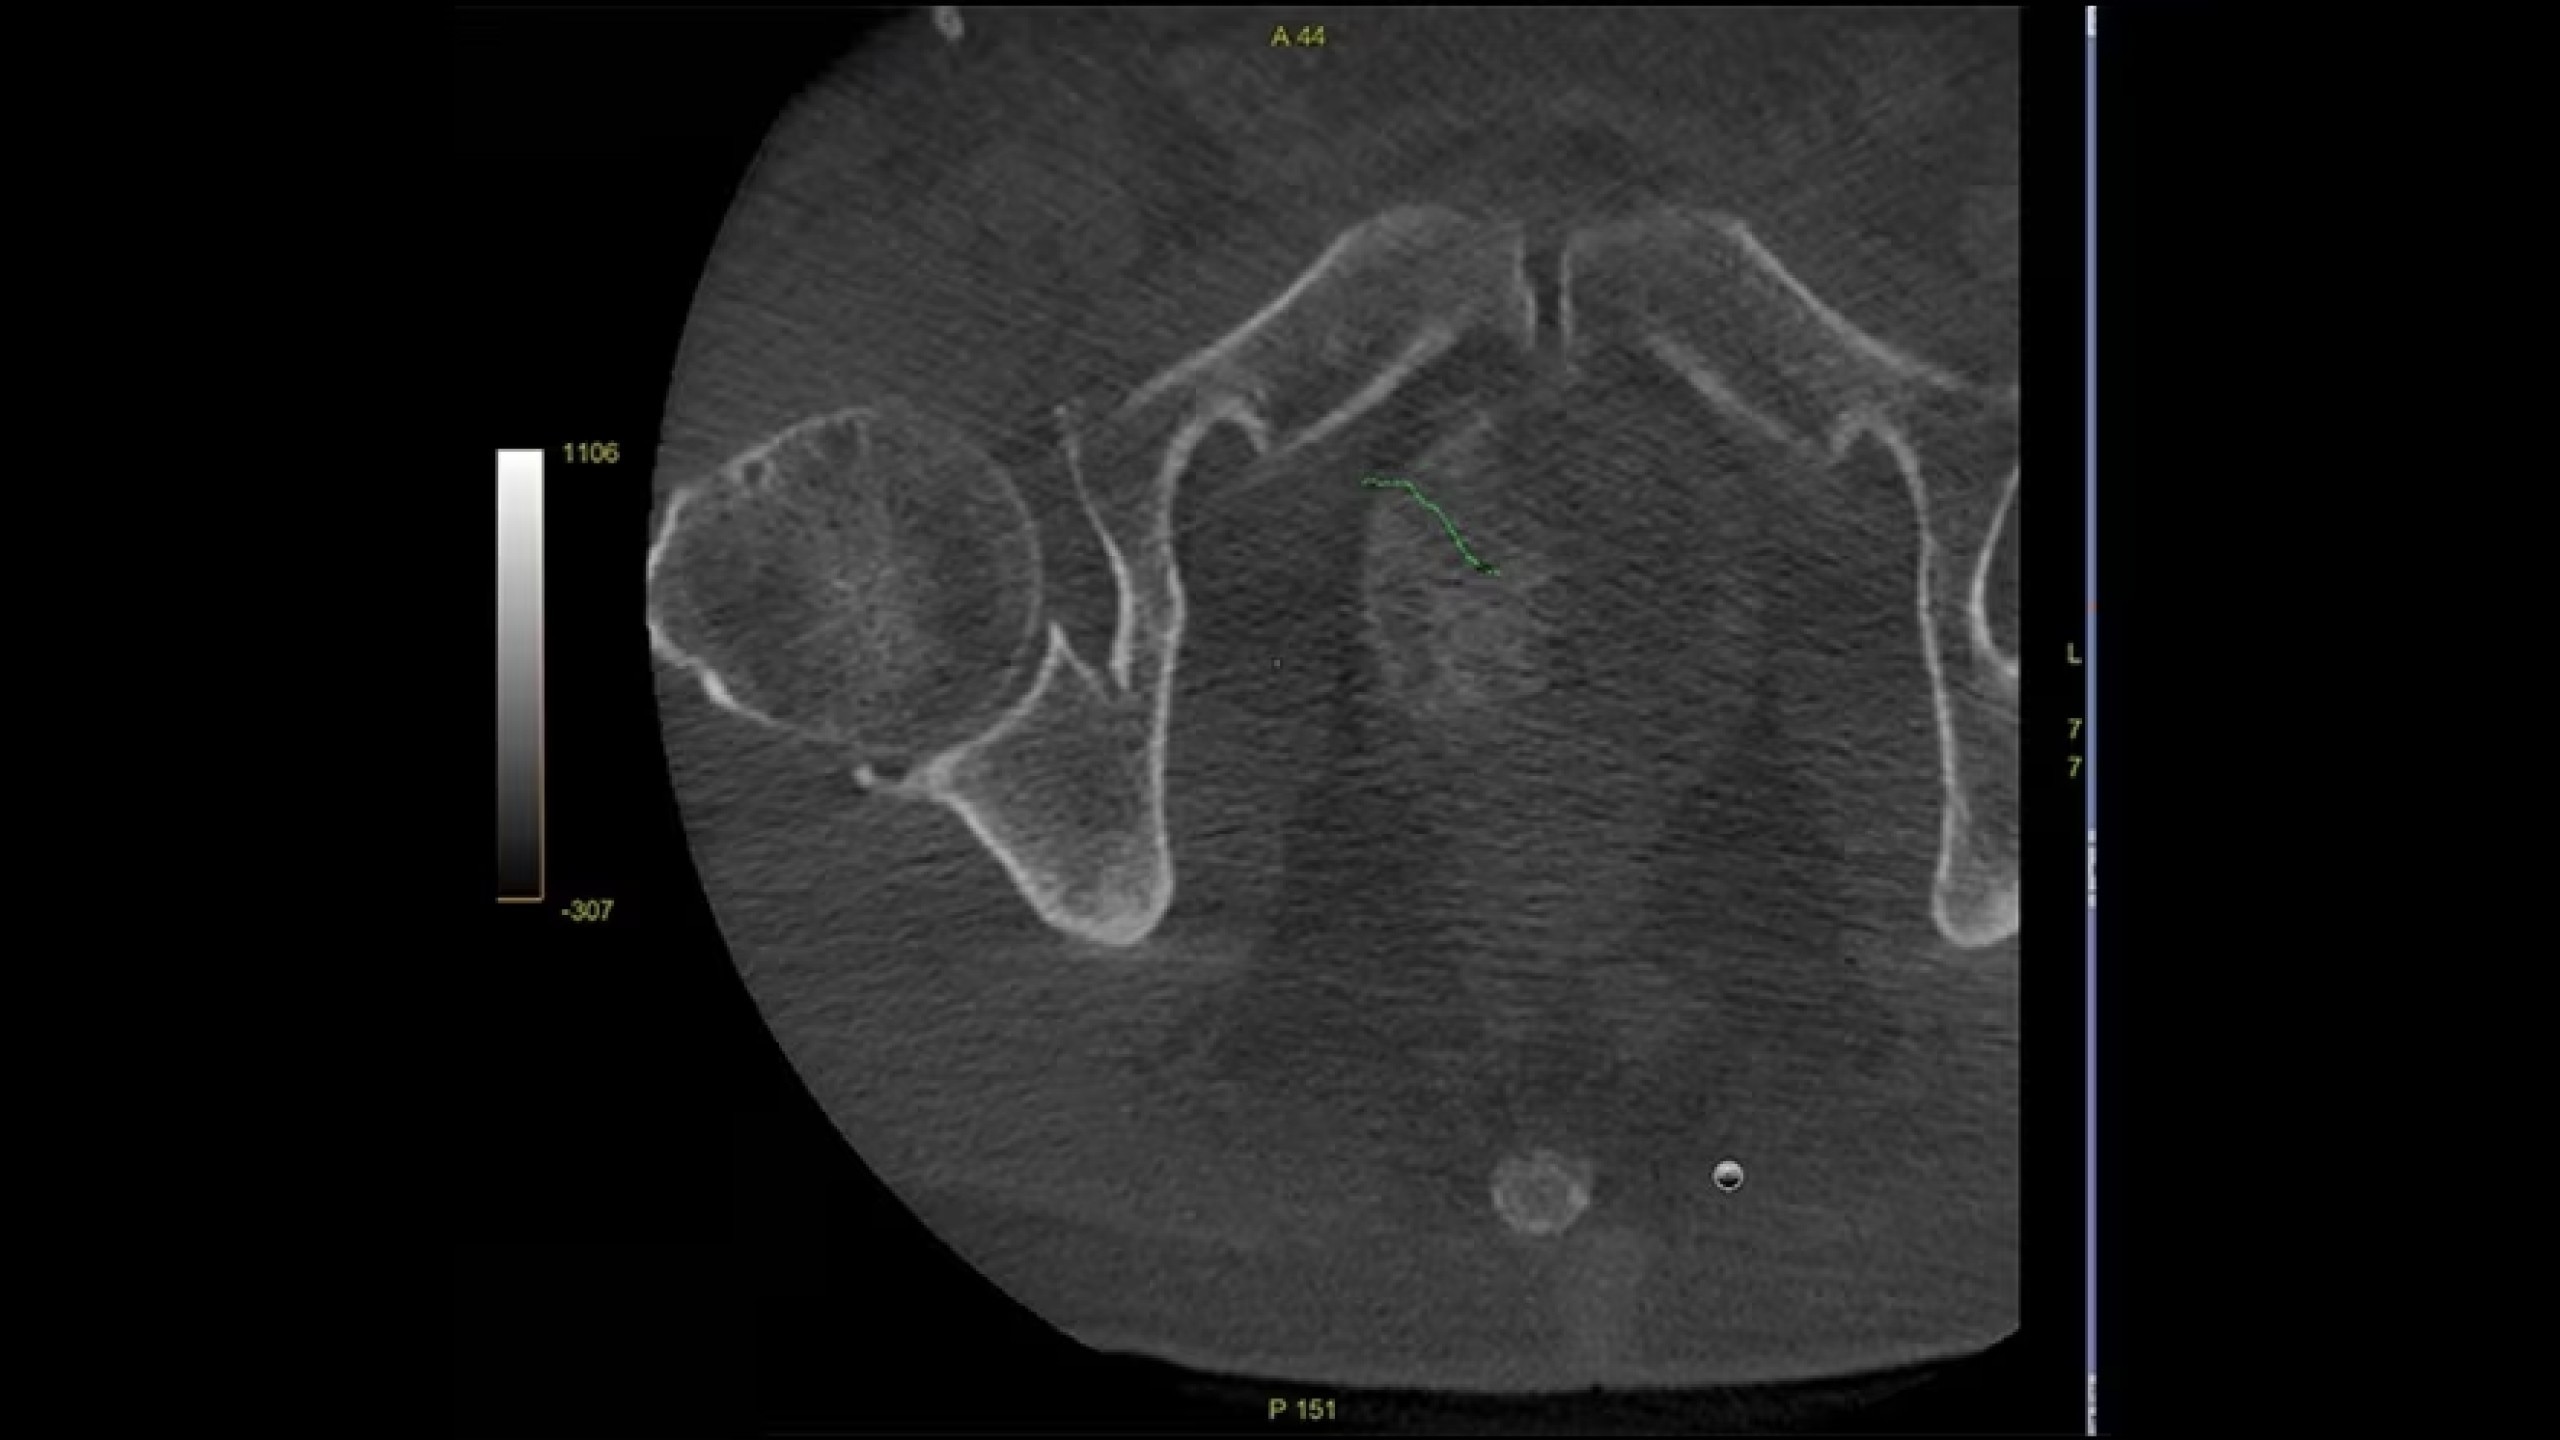

Embo ASSIST is an AI-based augmented guidance solution designed to define optimal embolization strategies and streamline your clinical workflow.

Segment vasculature from CBCT in one click

Improve speed and accuracy with Needle ASSIST.